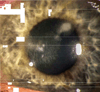

Results: Primary interface complications include infectious keratitis, diffuse lamellar keratitis, central toxic keratopathy, pressure-induced stromal keratopathy (PISK), and epithelial ingrowth. Infectious keratitis is most commonly caused by Methicillin-resistant Staphylococcus aureus (early onset) or atypical Mycobacterium (late onset) postoperatively, and immediate treatment includes flap lift and irrigation, cultures, and initiation of broad-spectrum topical antibiotics, with possible flap amputation for recalcitrant cases. Diffuse lamellar keratitis is a white blood cell infiltrate that appears within the first 5 days postoperatively and is acutely responsive to aggressive topical and oral steroid use in the early stages, but may require flap lift and irrigation to prevent flap necrosis if inflammation worsens. In contrast, PISK is caused by acute steroid response and resolves only with cessation of steroid use and intraocular pressure lowering. Without appropriate therapy PISK can result in severe optic nerve damage. Central toxic keratopathy mimics stage 4 diffuse lamellar keratitis, but occurs early in the postoperative period and is noninflammatory. Observation is the only effective treatment, and flap lift is usually not warranted. Epithelial ingrowth is easily distinguishable from other interface complications and may be self-limited or require flap lift to treat irregular astigmatism and prevent flap melt.